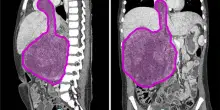

Sanità, gli over 65 assorbono più del 60% della spesa

In Italia la speranza di vita nel 2024 ha raggiunto gli 81,4 anni per gli uomini e 85,5 per le donne. Entro il 2050 salirà ancora di circa 3 anni, e un terzo della popolazione avrà...